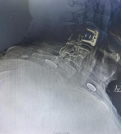

术前影像资料显示C3/C4椎间盘突出、极重度颈椎椎管狭窄、C5/6椎体融合